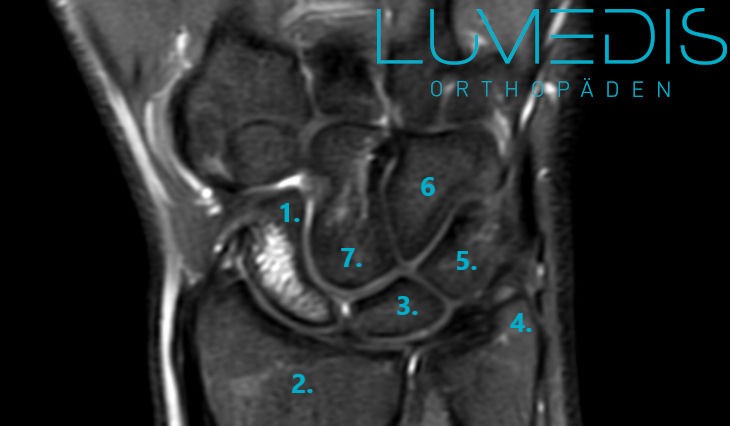

MRT eines Handgelenk mit Handwurzel mit Bandverletzung

Abbildung des TFCC am Handgelenk mit allen Bändern